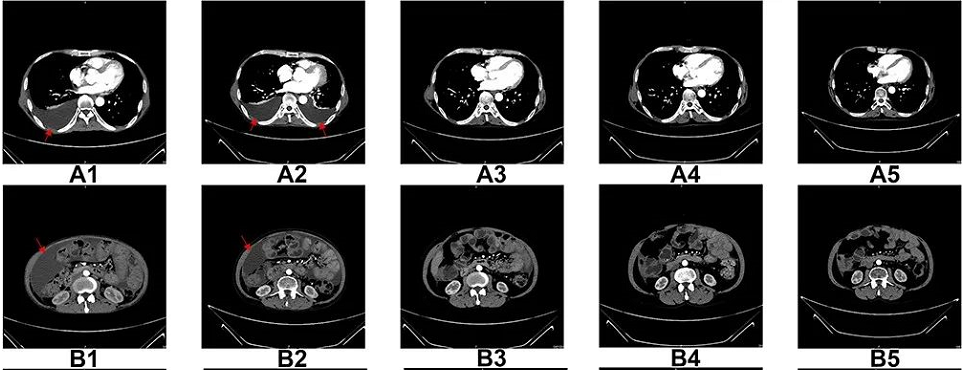

圖A1-A5:CT掃描顯示,6個(gè)療程后胸腔積液完全消失

圖B1-B5:CT掃描顯示,6個(gè)療程后腹水幾乎完全消失